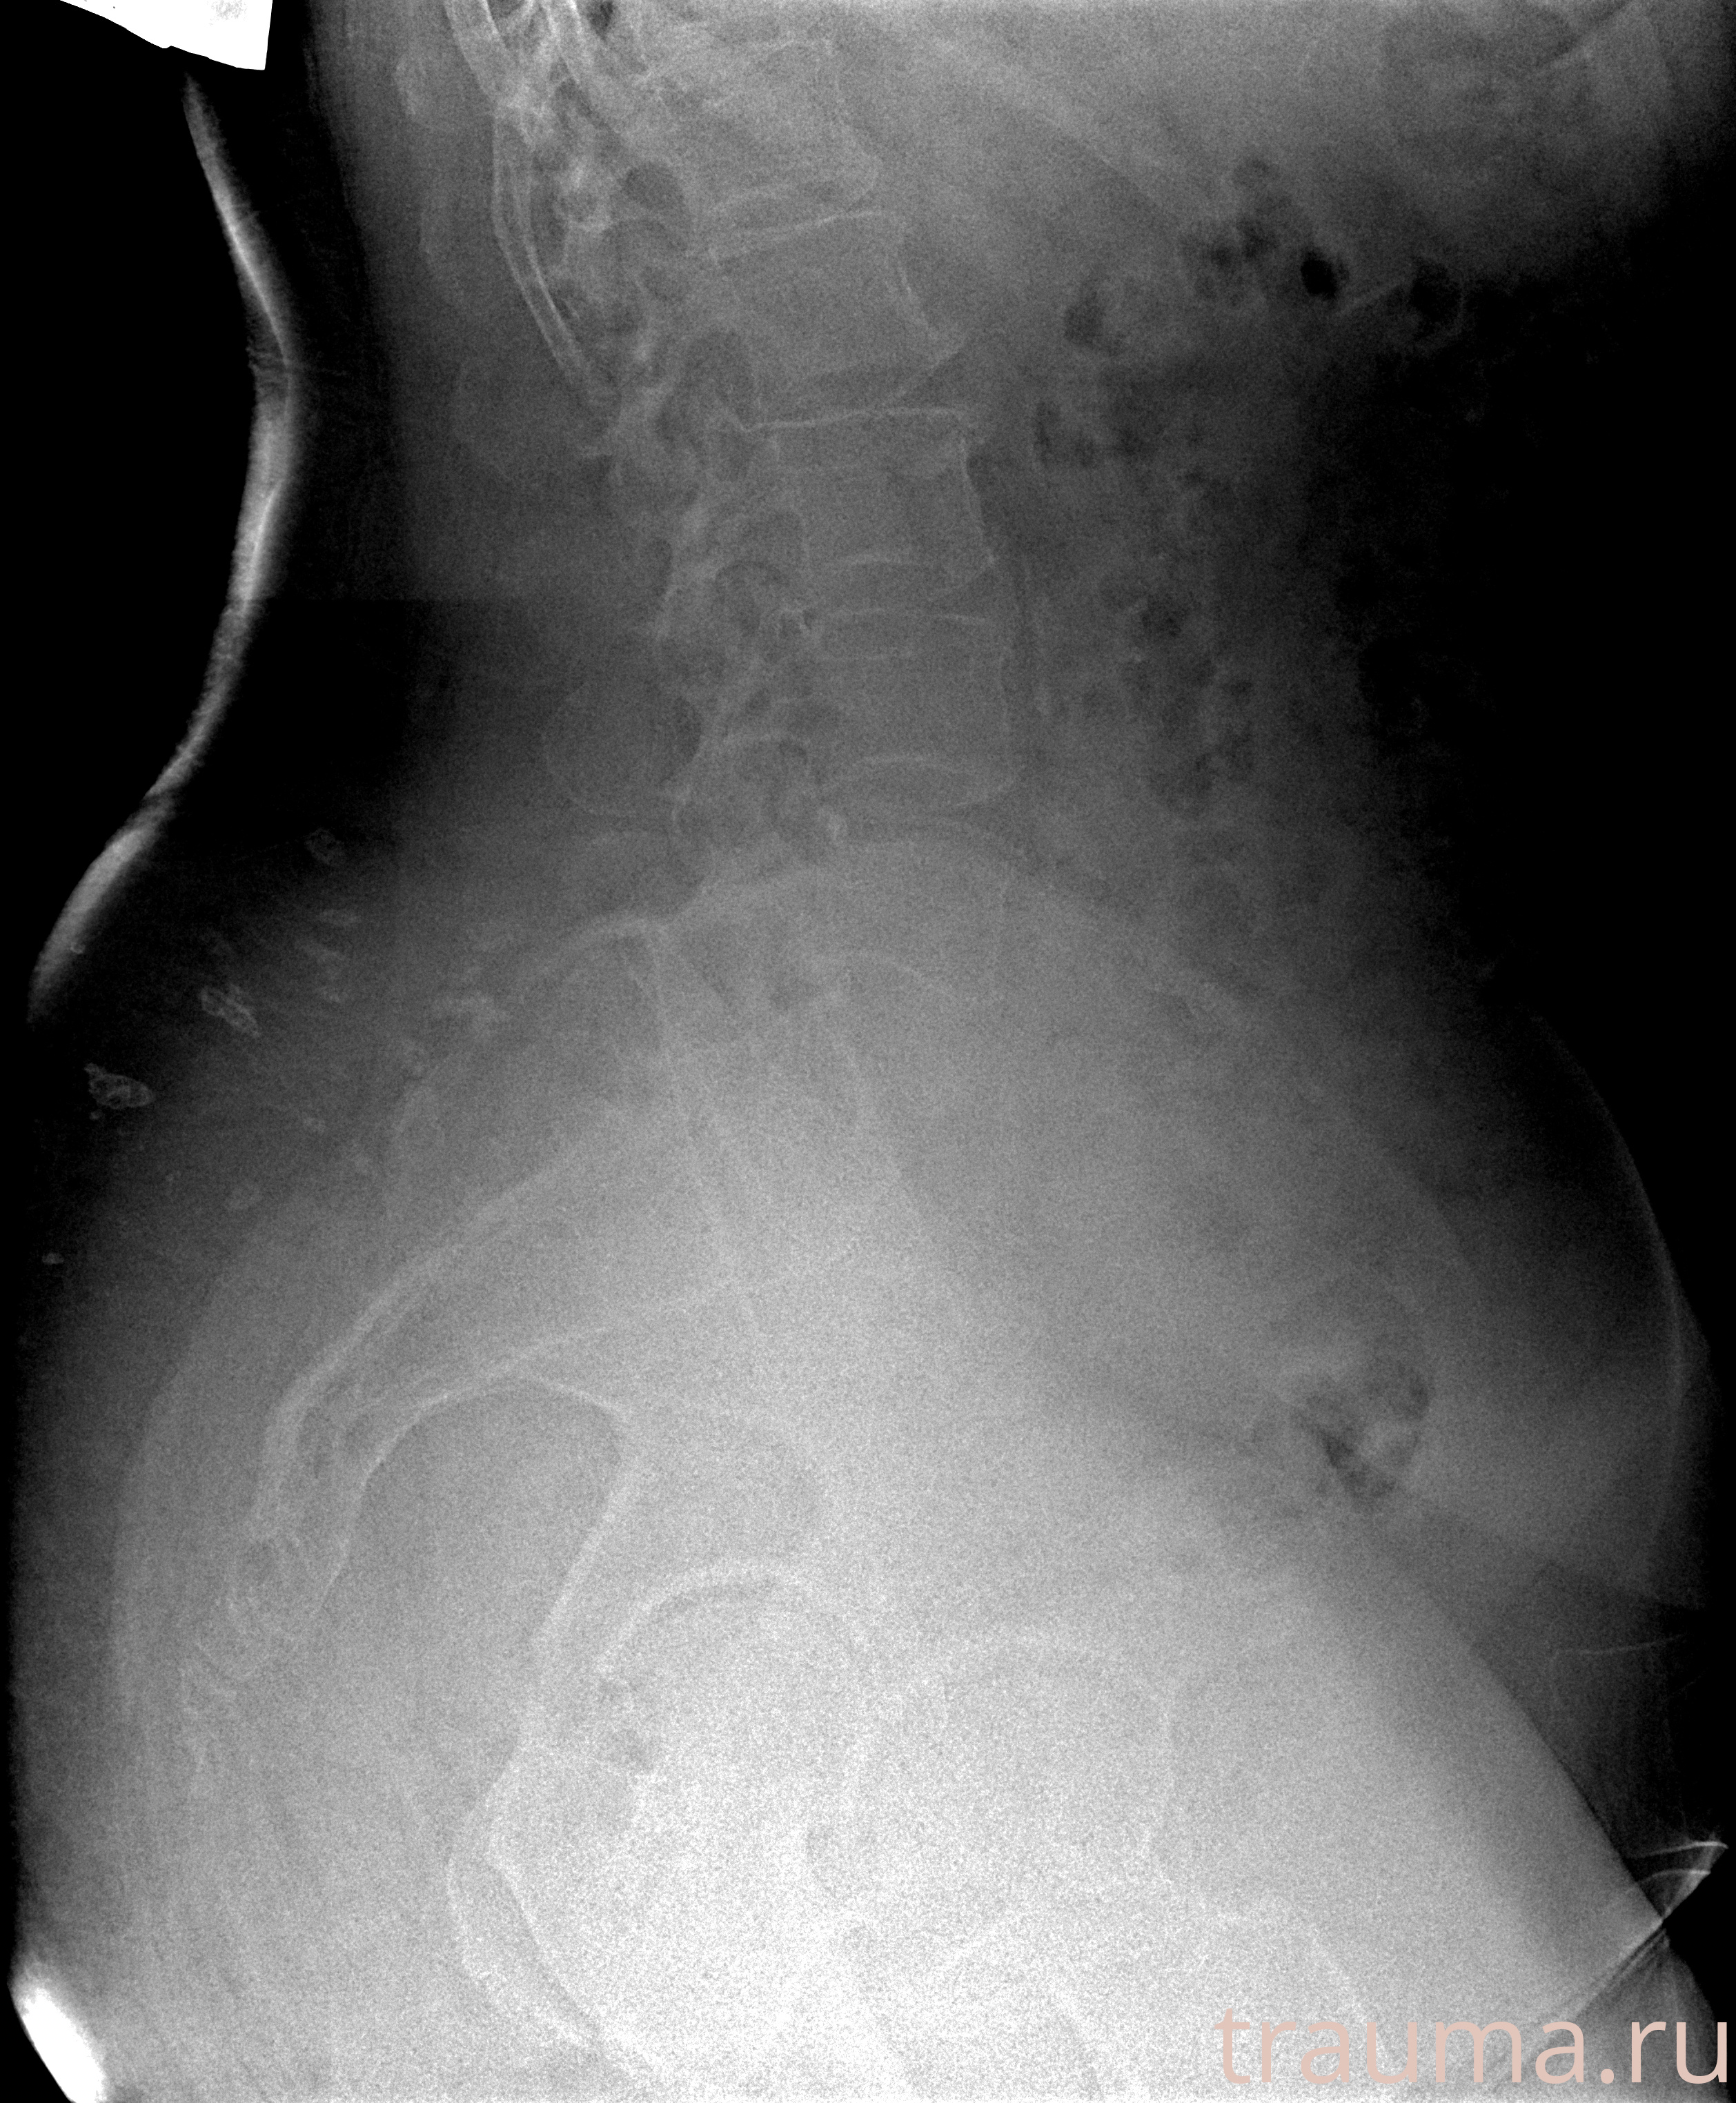

Рентген на дому: по вашему адресу приезжает врач-рентгенолог, травматолог-ортопед с мобильным рентгеновским аппаратом, проводит диагностику травмы или заболевания, делает необходимые рентгенограммы, дает рекомендации по дальнейшему лечению. Получить качественные снимки в домашних условиях возможно благодаря уникальной методике, разработанной МосРентген Центром для института  Склифосовского